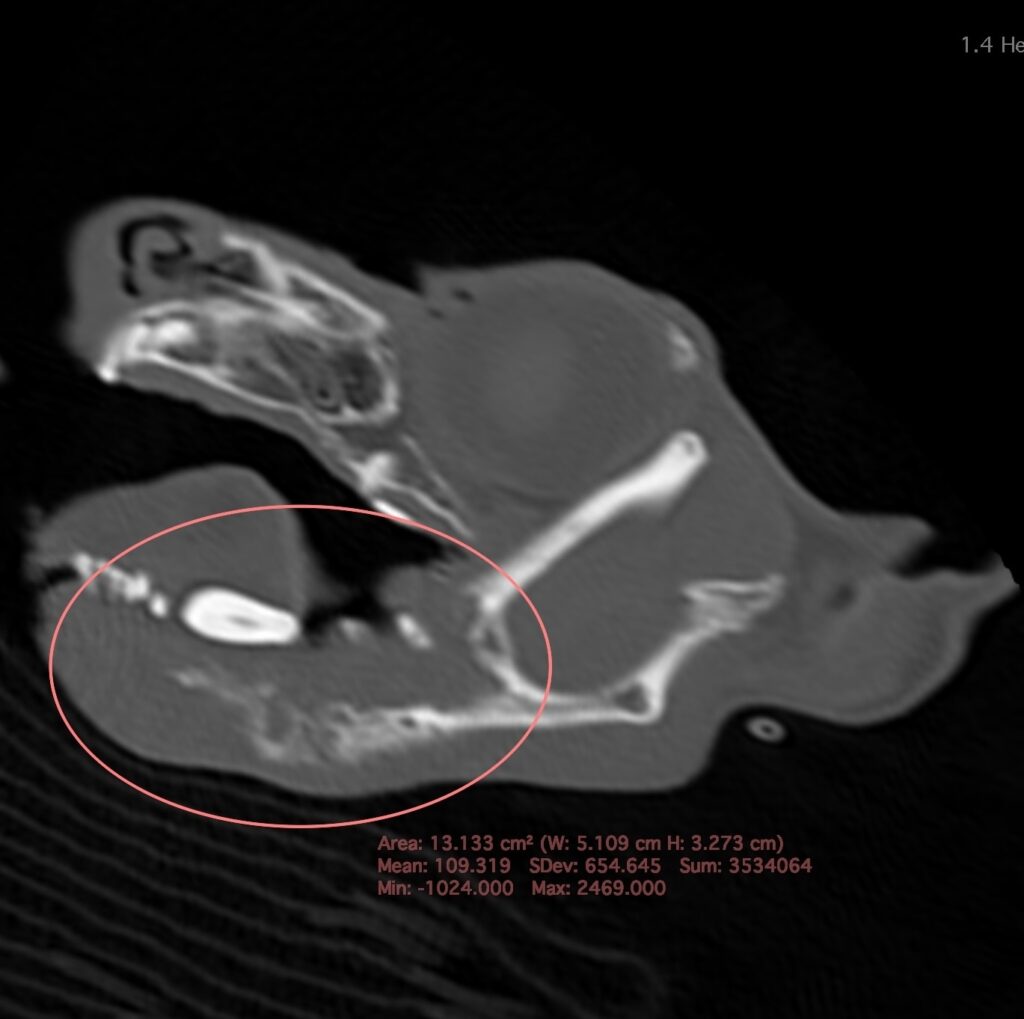

臨床経過と診察時の所見から下顎の腫瘍を疑い、2日後に全身麻酔下でのCT検査を行う。

CT検査で右下顎骨の骨融解、骨増生を認める。